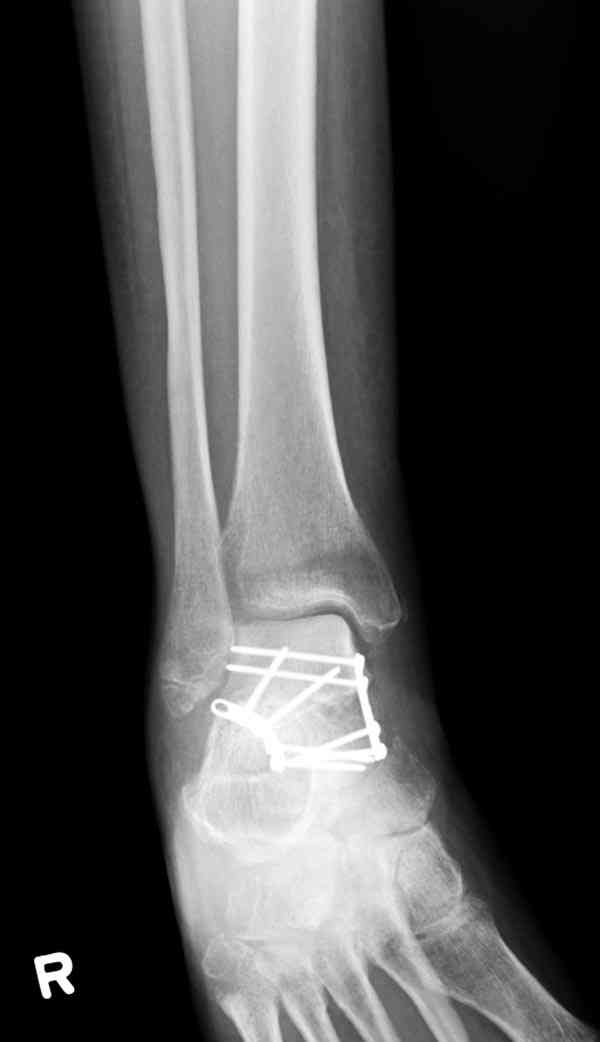

Решили не связываться с остеосинтезом, а сделать сразу берцово-пяточный блок. Снимки в приложении.

По завершении удлинения, наверно, заштифтуем.

Комментарии/критика приветствуются.